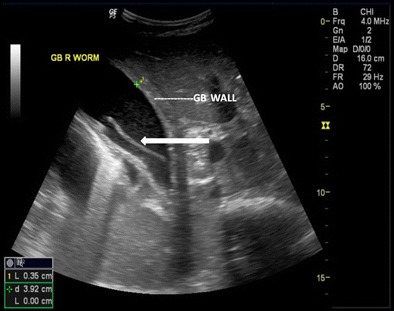

Gall bladder

Ascaris in the gallbladder is rare, constituting 2.1 % of hepatobiliary ascariasis [7]. This can be easily picked up on ultrasound. Inner tube may not be seen (Strip sign). Live worms may move within the gall bladder. The ascaris may be seen as a coil of worm in the gall bladder lumen (Fig. 7). The worm in the gall bladder may also present with cholecystitis (Fig. 8).

Fig. 8.

A 25-year-old male with acute right hypochondriac pain showing ascaris (thick white arrow) inside the gall bladder. Note GB wall thickening and luminal sludge indicating acute cholecystitis